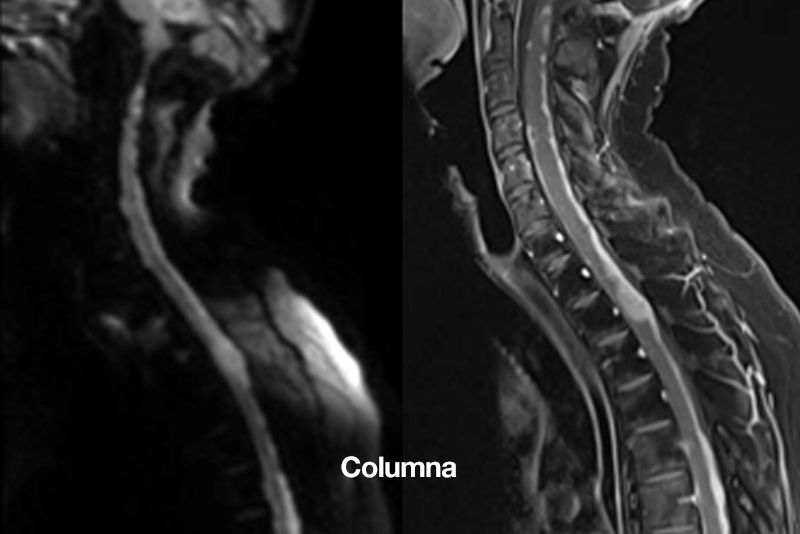

Columna